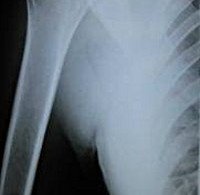

Рентгенография плечевой кости

Рентгенография костей. Рентгенологическое исследование, показанием которого является подозрение на перелом ствола, периостит, остеомиелит, доброкачественную или злокачественную опухоль плечевой кости. Стандартный тест проводится в двух планах (прямой и боковой вид). В некоторых случаях сначала делается снимок в одной проекции, а после обнаружения патологии назначается второе рентгеновское изображение для объяснения природы и местоположения поражений. Требуется специальное обучение. В детстве и во время беременности обычные рентгеновские снимки заменяются другими методами (КТ, МРТ). При наличии аварийных показаний нет никаких ограничений по тесту.

В травматологии рентгенография плечевой кости назначается при подозрении на перелом плечевого ствола, остеомиелит или периостит. В других областях медицины (онкология, хирургия, ортопедия) методика может быть использована для выявления пороков развития, злокачественных и доброкачественных опухолей и оценки участия костных структур плеча в гнойно-воспалительном процессе. Противопоказанием к планируемому исследованию считается возраст детей и срок беременности. При неотложной патологии, угрожающих жизни состояниях, невозможности использования других инструментальных методов диагностики (МРТ, КТ, УЗИ) противопоказаний нет.